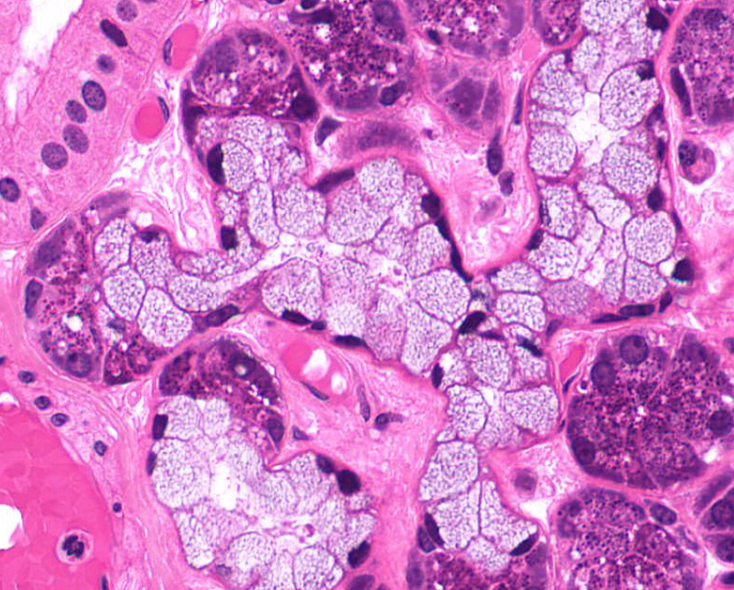

exocrine cells of the pancreas

secrete insulin and glucagon

shaped like a slice of pie

structure

islet of Langerhans of the pancreas

endocrine cell

secrete hormones for digestion